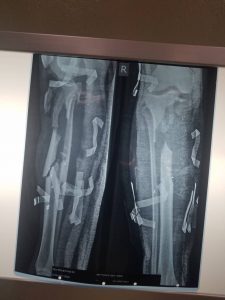

اجرى فريق طبي جنوبي بالتنسيق مع الدائرة الصحيه للدعم والإسناد اليوم الثلاثاء في مستشفى أطباء بلا حدود في العاصمة عدن عملية جراحية نوعية لاحد جرحى الجيش الجنوبي اصيب في معارك ابين تمثلت في زراعة عظمة الشظية كبديل لعظمة القصبة في الساق وإصلاح العضلات والاعصاب والأوعية الدموية.

وتطرق الداعري إلى مراحل إجراء العملية حيث أوضح بأن الشاب أصيب في ساقه الأيمن أدى إلى فقد جزء من عظمة الساق وتهتك في العضلات والأنسجة ،حيث اسعف الى عدد من المستشفيات في عدن وقرر له الأطباء بتر ساقه نتيجة لحالة الإصابة البليغة ،وتابع مدير الدائرة الصحية تم عرض الحالة على أحد كوادر الدائرة الصحية استشاري في العظام والمفاصل وبعد المعاينة قام بإجراء عملية جراحية اولى لتنظيف جرح ملوث وعضلات متهتكة وعظمة الساق المهشمة،وبعد ثلاثة أيام من إجراء العملية الأولى ادخل مرة أخرى غرفة العمليات وأجريت له عملية تقييم الساق وتنظيفة،وبعد ستة أيام أجريت له عملية ثالثة تم تقييم الجرح من خلال المحافظة على نظافته والحفاظ على ساقه وتجنب بترها من الركبة ،بعدها قرر تعويض العظم المفقود بنقل عظمة الشظية ومن ثم تثبيت الساق بمثبت خارجي، مؤكدا بأن هذه العملية تعد كبرى ومعقدة .